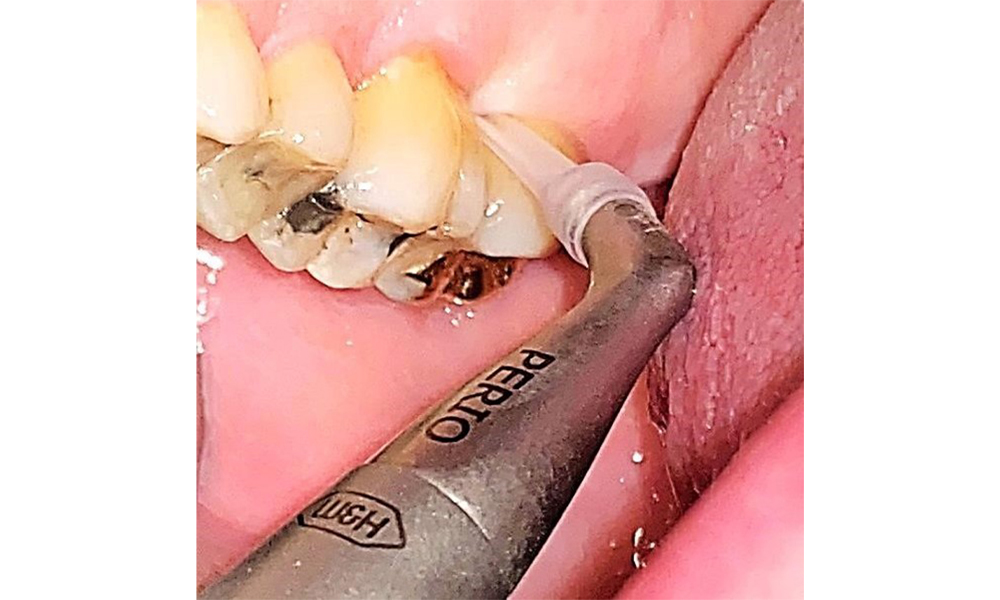

There are no limitations regarding the choice of instrumentation methods. Regular supragingival and subgingival instrumentation is essential to prevent disease progression due to the pre-existing periodontitis and high risk of recurrence. There are no limitations placed on the selection of instruments for mechanical biofilm removal from a general medical perspective, and removal should be performed as needed. Hard and mineralized plaque, such as calculus and concretions, should be removed using manual instruments or sonic/ultrasonic scalers (Fig. 9) (8, 9).

Use an ultrasonic tip to remove hard, mineralized plaque (Proxeo Ultra scaler with the Perio tip, W&H, shown here). © Dr R. Krapf

Fig. 9: Use an ultrasonic tip to remove hard, mineralized plaque (Proxeo Ultra scaler with the Perio tip, W&H, shown here). © Dr R. Krapf

Supragingival and subgingival biofilm removal is indispensable for maintaining the stability of the periodontal condition. Air polishing using low-abrasive powder is suitable for this purpose. Periodontal pockets and exposed root surfaces must be cleaned with low-abrasion powders. The use of a flexible parotip is recommended for patients with increased probing depths (deeper than 5 mm) (Fig. 10). (9)

Subgingival application of the flexible air polisher tip (Proxeo Aura, W&H, shown here) to the mesiopalatal aspect of tooth 27 with a periodontal pocket depth of 5 mm. © Dr R. Krapf

Fig. 10: Subgingival application of the flexible air polisher tip (Proxeo Aura, W&H, shown here) to the mesiopalatal aspect of tooth 27 with a periodontal pocket depth of 5 mm. © Dr R. Krapf